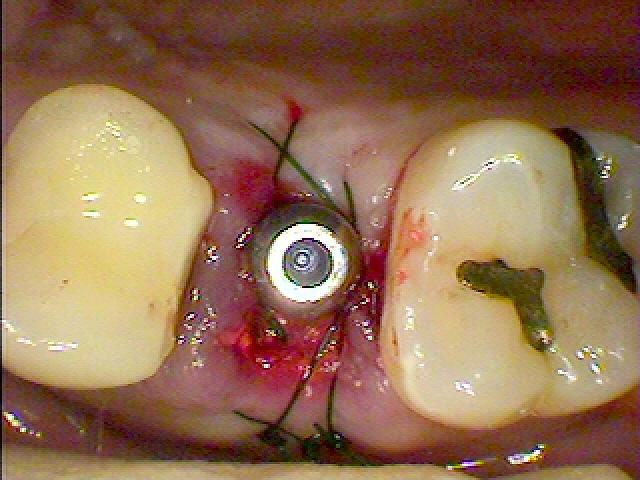

縫合して終了となります

縫合して終了となります